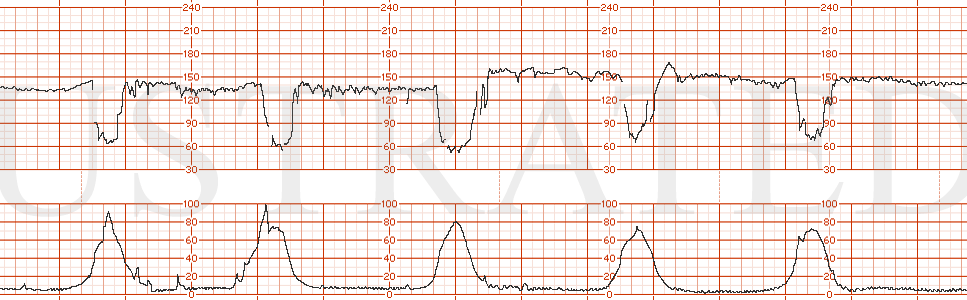

STRIP 22

1. The fhrt is as follows: (baseline hr 150 bpm, normal variability, one acceleration. 1 classic late deceleration is seen in a series of 5 contractions occurring over a 10 minute window. (the late decelerations are too deep (some are nadiring at 50-60 bpm below baseline. Normal lates are more subtle usually 10-30 bpm at most below baseline)